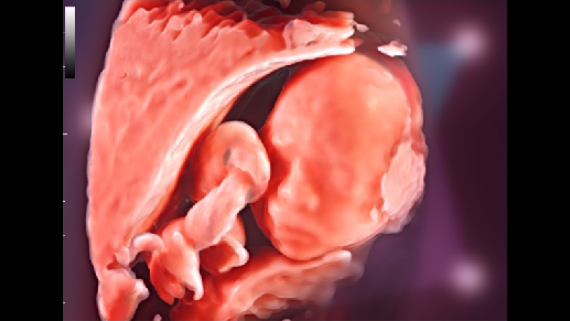

ImĂĄgenes clĂnicas